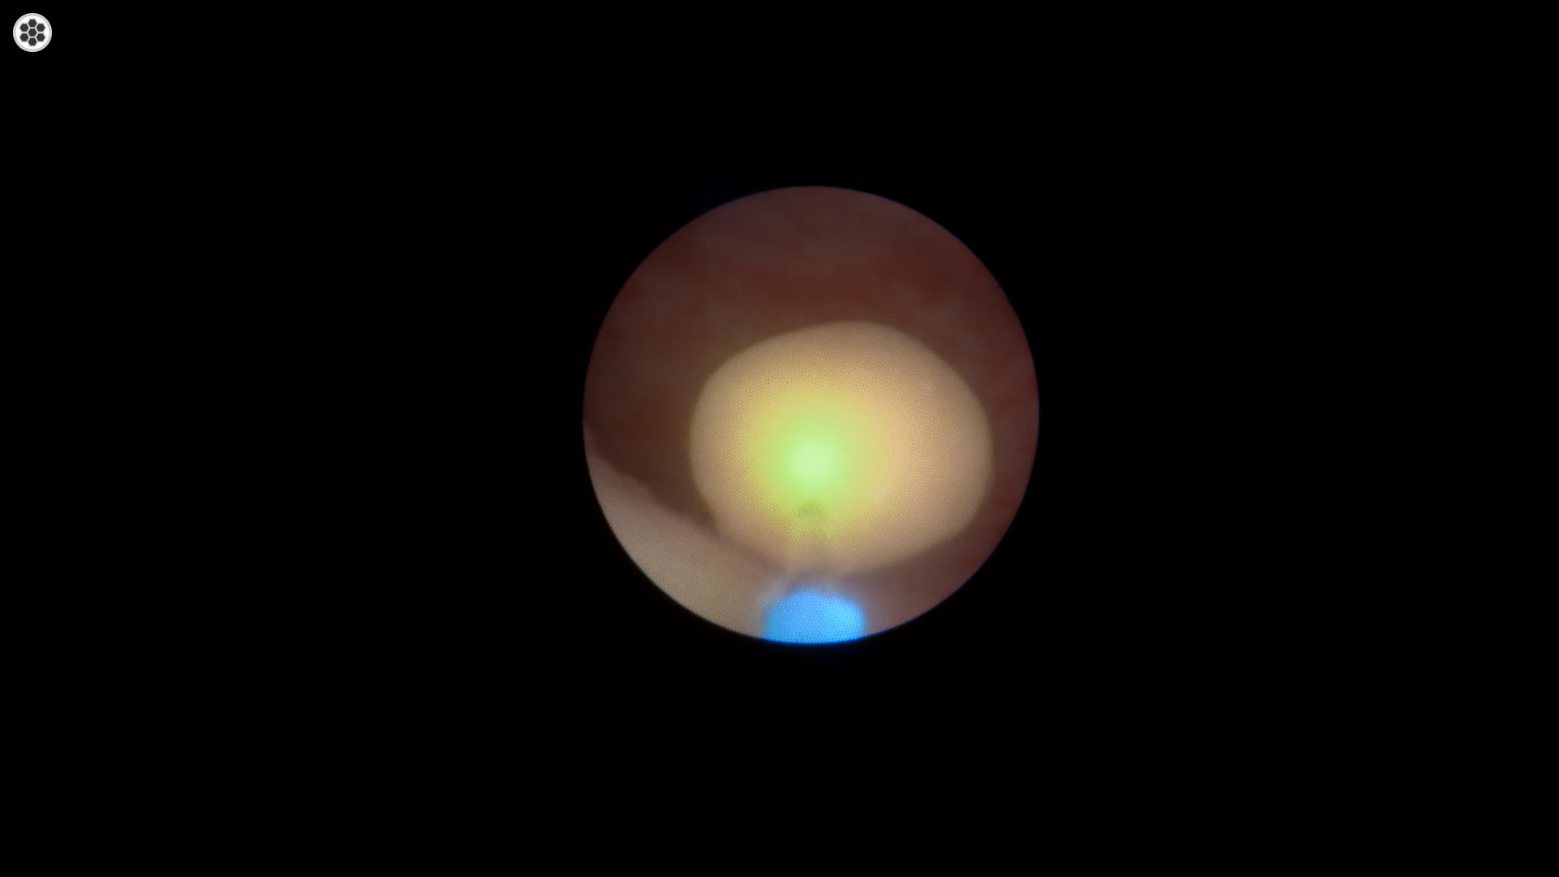

복강경 난소자궁적출술

복강경을 통한 최소침습 난소자궁적출술 과정입니다. 1-2cm의 작은 절개를 통해 고화질 카메라와 정밀한 수술 기구를 사용하여 안전하고 정확하게 수술을 진행합니다.

고화질 내시경 카메라를 통해 복강 내 장기들을 확대하여 관찰할 수 있어 더욱 정밀한 수술이 가능하며, 혈관과 난소, 자궁을 정확하게 확인하여 안전하게 제거할 수 있습니다.

고화질 내시경 카메라로 확대된 영상을 통해 더욱 정밀하고 안전한 수술을 시행합니다.